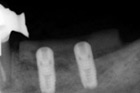

Predimplantološka regenerativna kirurgija

Najèešæi ogranièavajuæi faktor u dentalnoj implantologiji je nedostatak kosti alveolarnog grebena. Dr. Krmpotiæ se u svome klinièkom radu posebno posvetio toj problematici. U našoj svakodnevnoj praksi nudimo operacije podizanja dna sinusa, regeneracije kosti alveolarnog grebena, distrakcije i osteoplastike- presaðivanje kosti. Naše znanje, klinièko iskustvo i opremljenost omoguæavaju rješavanje i najnepovoljnijih sluèajeva.

Osteoplastika

Podizanje dna sinusa